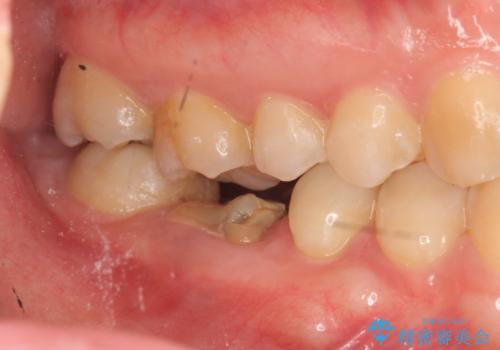

- 虫歯を数年放置した結果、痛みがひどくなり治療を希望され来院されました。

根だけ残った歯は、破折があり急性の炎症が認められ抜歯が必要な状態です。

抜歯後は、前後の歯を削らずにしっかりと咬合力を回復できるインプラント治療を選択されました。

虫歯の放置により吸収してしまった骨も造成を行うことでインプラント周囲環境をしっかりと整えています。